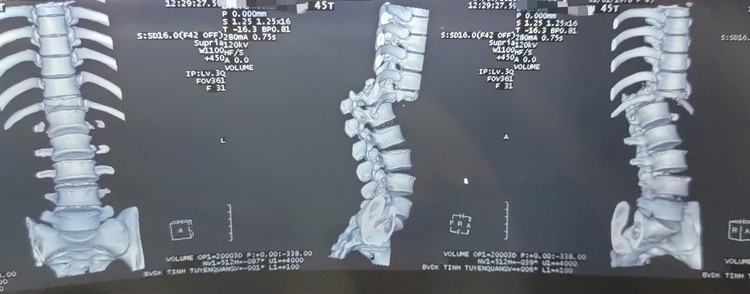

Kết quả chụp phim CT-Scanner (cắt lớp vi tính) cho thấy bệnh nhân bị gãy đốt sống T12, phần dưới trượt ra sau độ IV rất nặng. Bệnh nhân được hội chẩn liên khoa và được chuyển đến khoa Ngoại Thần kinh của Bệnh viện để điều trị.

Cột sống bị gẫy và đứt tủy sống trên phim chụp |

Cột sống bị gẫy và đứt tủy sống trên phim chụp